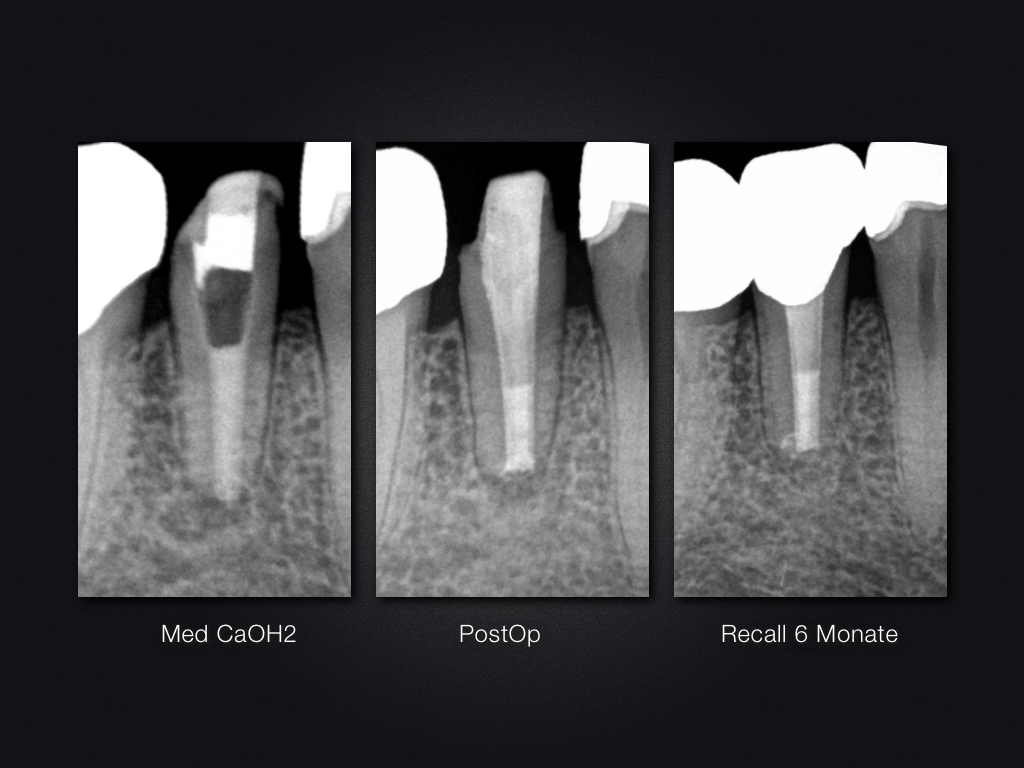

Ofenrohr- das Recall (2)